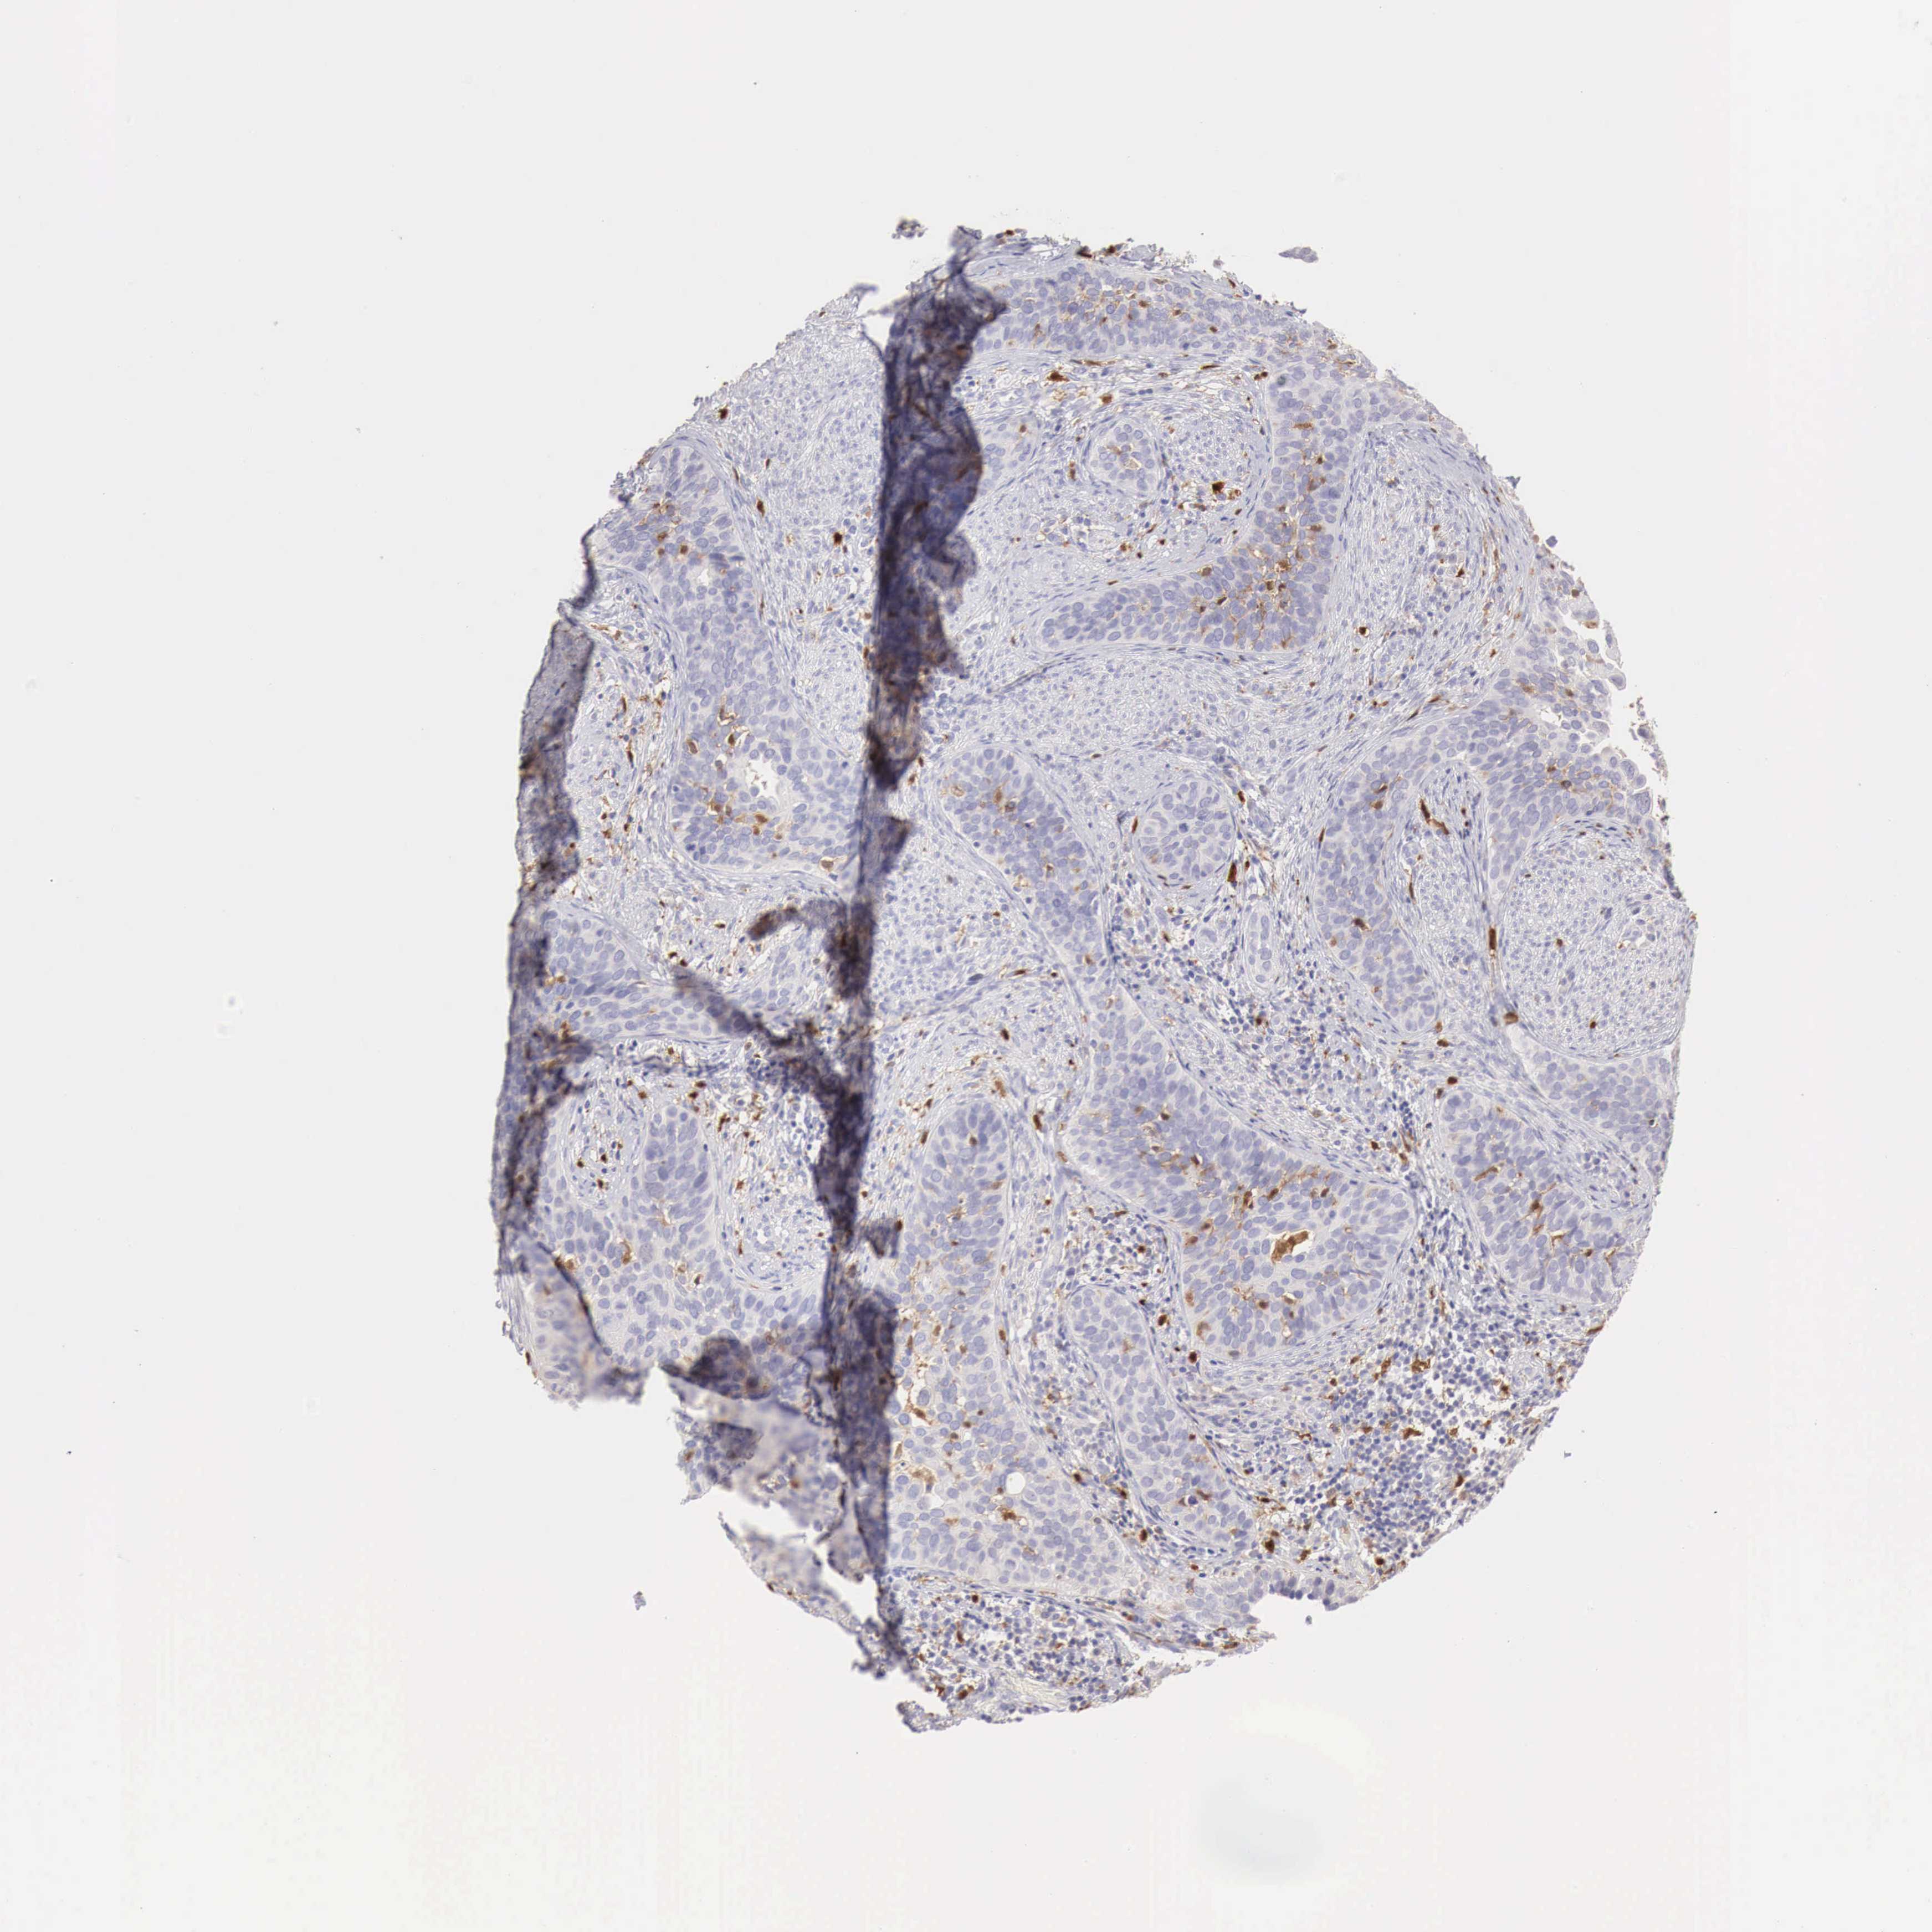

CERVICAL CANCER - Protein expressioni

A mouse-over function shows sample information and annotation data. Click on an image to view it in a full screen mode. Samples can be filtered based on level of antibody staining by selecting one or several of the following categories: high, medium, low and not detected. The assay and annotation is described here.

Note that samples used for immunohistochemistry by the Human Protein Atlas do not correspond to samples in the TCGA dataset.

Antibody stainingi

Antibody staining in the annotated cell types in the current human tissue is reported as not detected, low, medium, or high, based on conventional immunohistochemistry profiling in selected tissues. This score is based on the combination of the staining intensity and fraction of stained cells.

Each image is clickable and will lead to virtual microscopy that enables deeper exploration of all samples and also displays staining intensity scores, fraction scores and subcellular localization as well as patient and tissue information for each sample.

Antibody HPA000428

Antibody HPA000522

Staining

High

Medium

Low

Not detected

Intensity

Strong

Moderate

Weak

Negative

Quantity

>75%

75%-25%

<25%

None

Location

Nuclear

Cytoplasmic/membranous

Cytoplasmic/membranous,nuclear

Adenocarcinoma, NOS

Squamous cell carcinoma, NOS